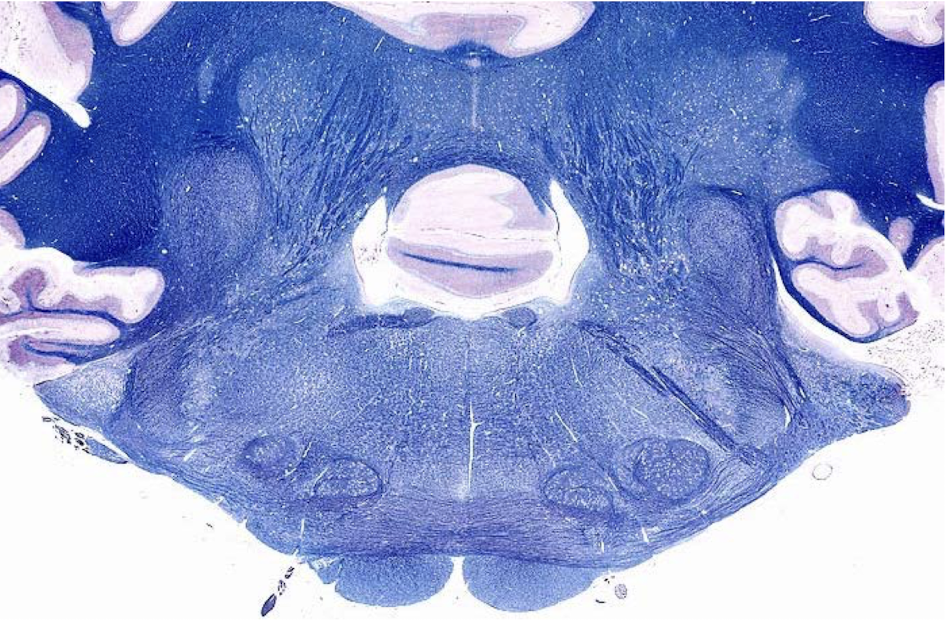

what section of the brain is shown?

rostral medulla

- closed 4th ventricle

- trapezoid body

- pyramids